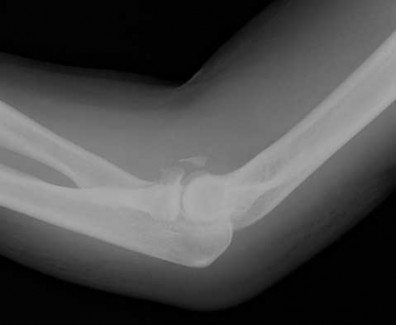

A patient has an elbow injury that includes a coronoid fracture, medial collateral ligament injury, and a radial head fracture. When is excision of the radial head without replacement indicated as definitive treatment for the radial head injury?

Excision is generally not indicated in this clinical scenario Corrent answer: 5

The injury likely represents a terrible triad injury. Restoration of the lateral column is required to restore valgus stability. A repaired or replaced radial head is also thought to be protective of the coronoid fracture repair. Therefore, excision is not indicated. Either radial head arthroplasty or open reduction and internal fixation would be indicated.